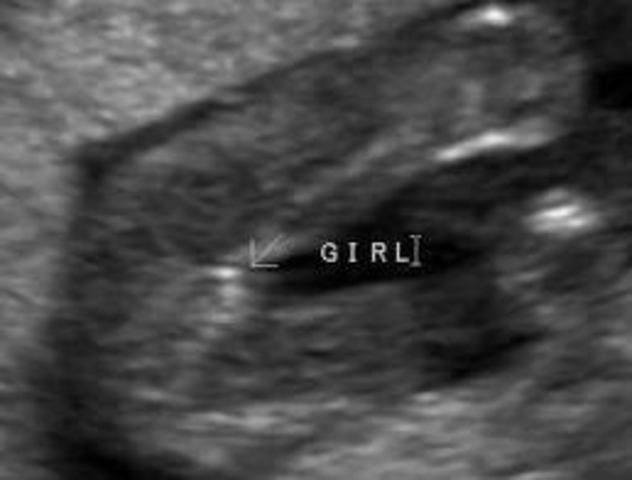

• Prenatal #3 Sex of Baby Apparent

Prenatal #3 Sex of Baby Apparent

Physical Development

The sex of the baby is only apparent after 10-12 weeks. Although it's decided during conception both male and female babies are identical during initial development.

Image taken from pregnancy.about.com